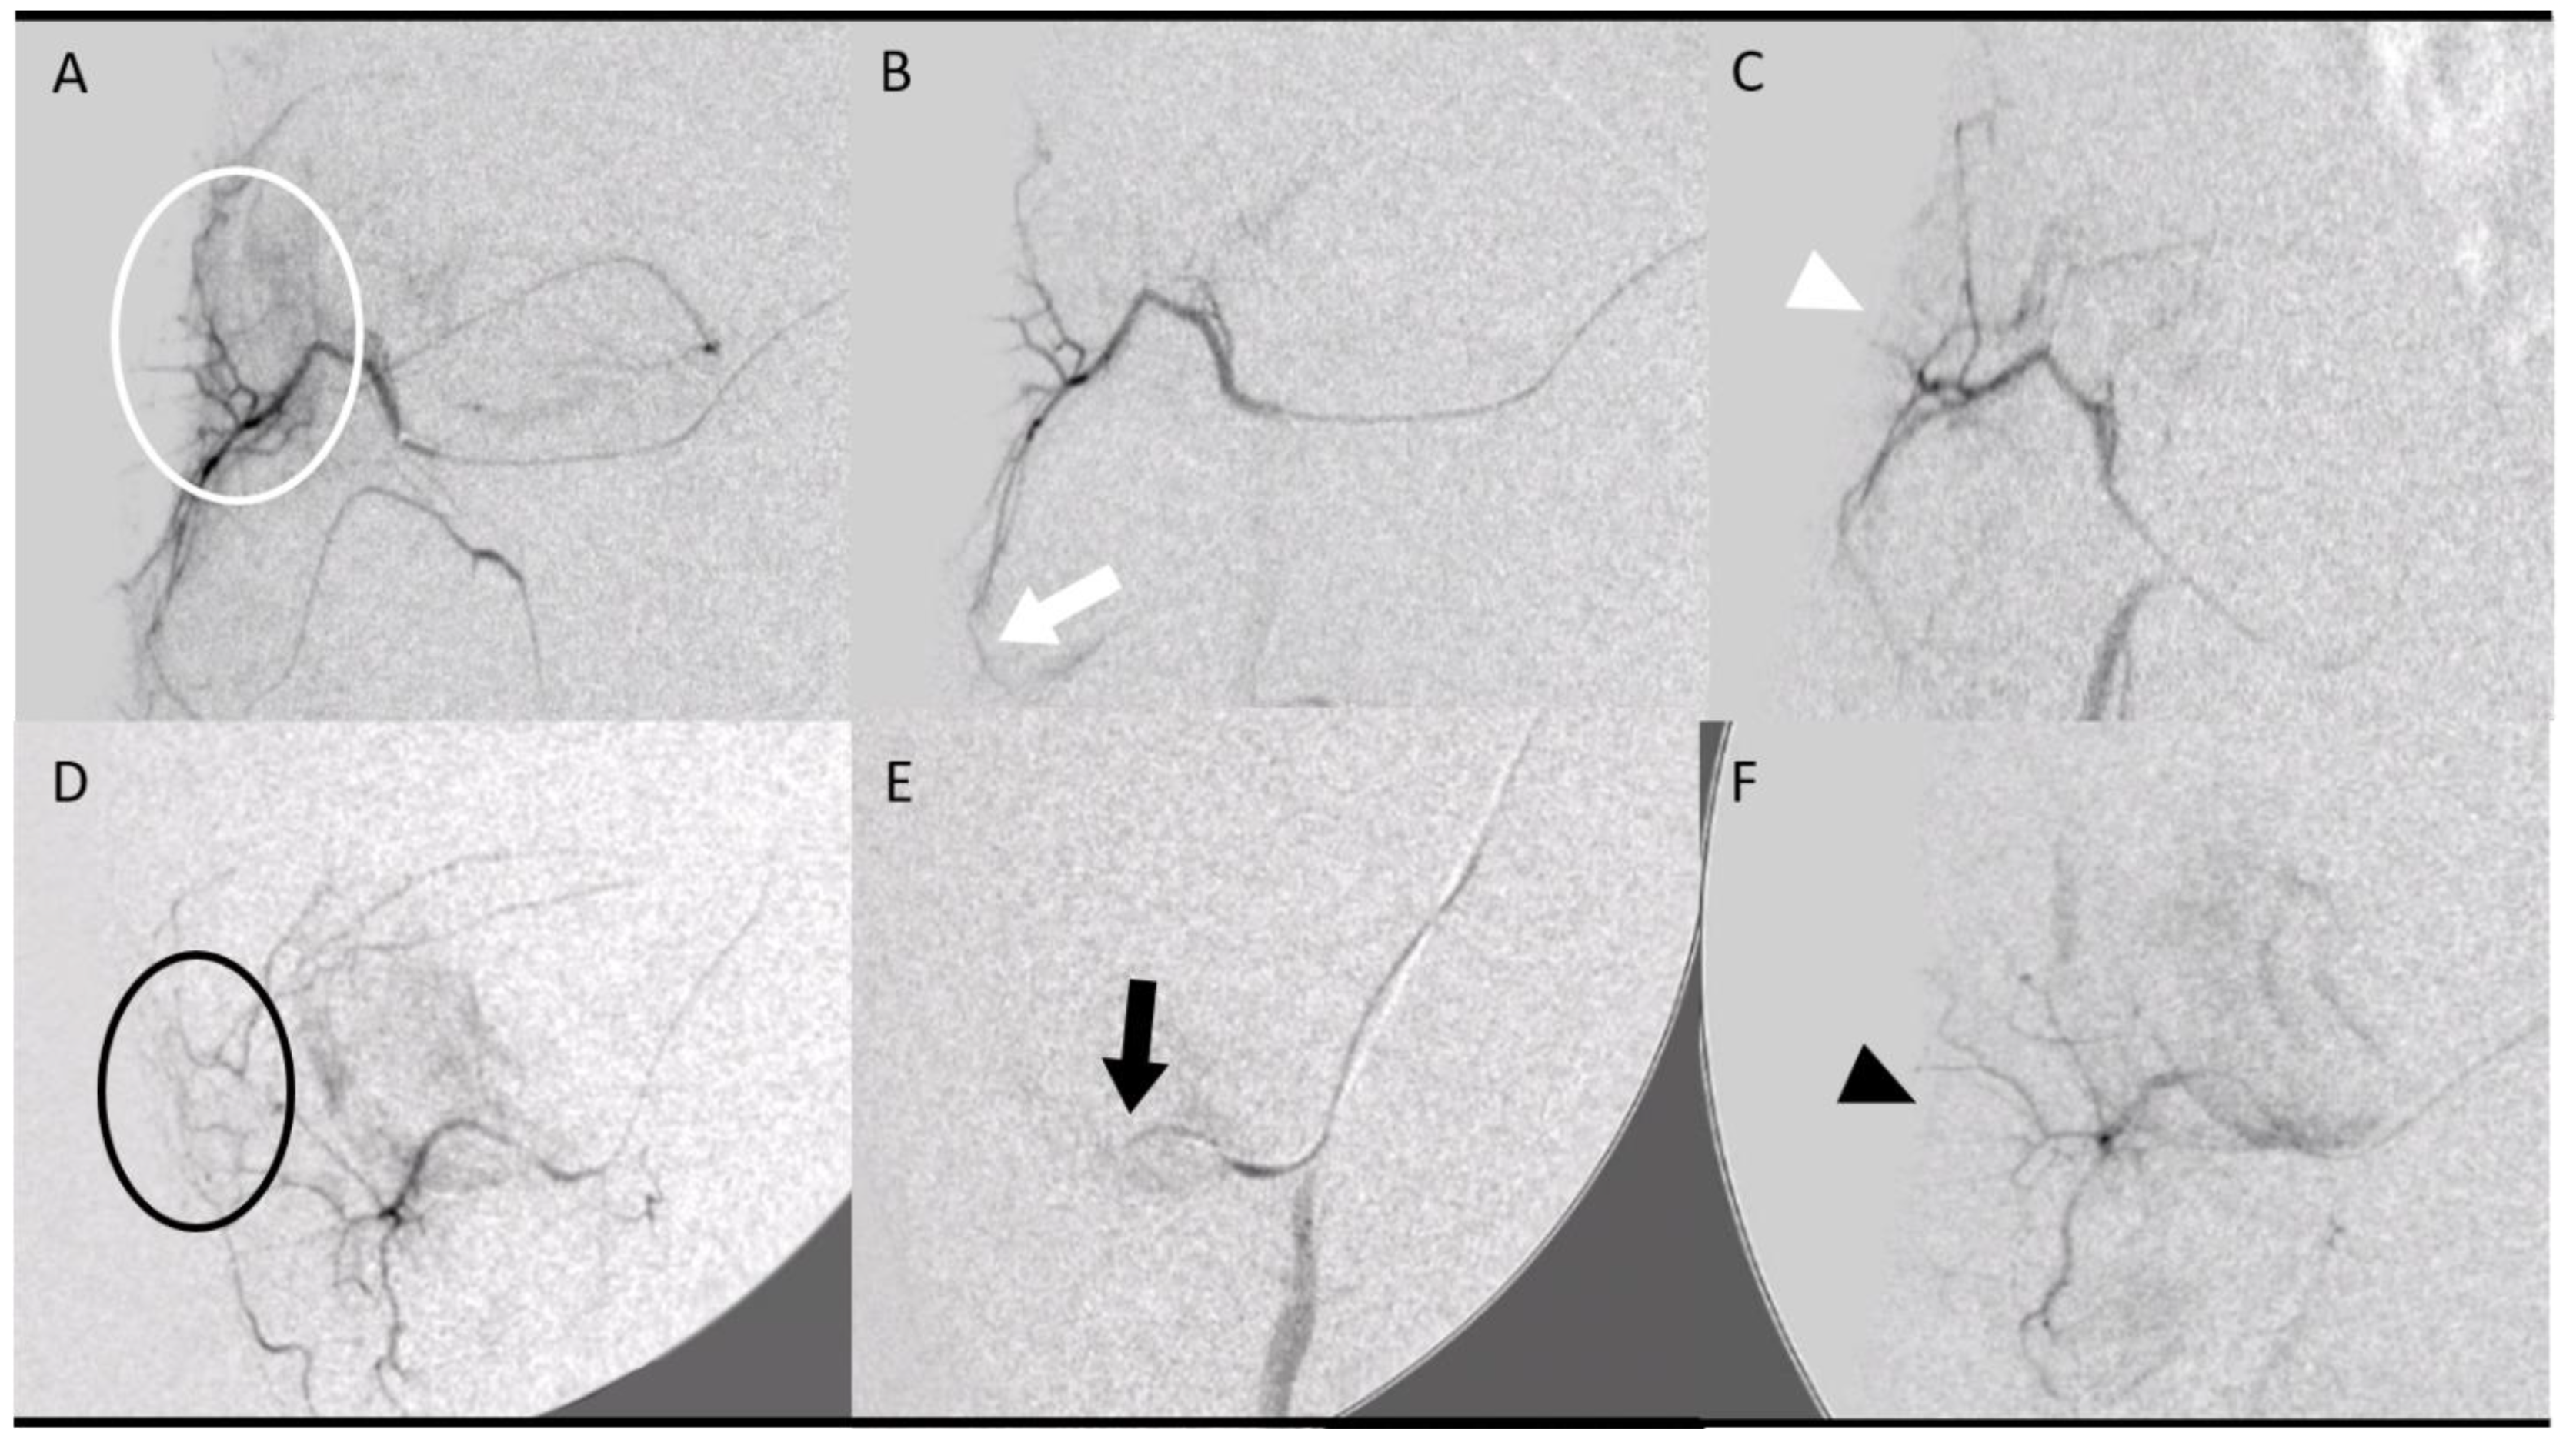

- Two groups (4 pigs, 8 tendons, 4 tendons in each group) were embolized with calibrated Embosphere® microspheres (Merit Medical, Paris, France) of either 50 to 100 µm (50–100 µm group) or 100 to 300 µm (100–300 µm group) diameter at D7 after collagenase injection. The microspheres were diluted to the 1/20th in NaCl and iodinated contrast was injected 0.1 per 0.1 mL according to the “pruning” technique [17] (Figure 2).

- The fourth group (2 pigs, 4 tendons) was embolized at D7 using an emulsion of imipenem/cilastatin (IMP/CS group) (500/500 mg) diluted in 10 mL of Visipaque iodinated contrast (GE Healthcare, Marlborough, MA, USA). The mixture was injected 0.1 per 0.1 mL until complete stasis of the feeding artery according to the Martinez et al. technique [18] was achieved (Figure 2).